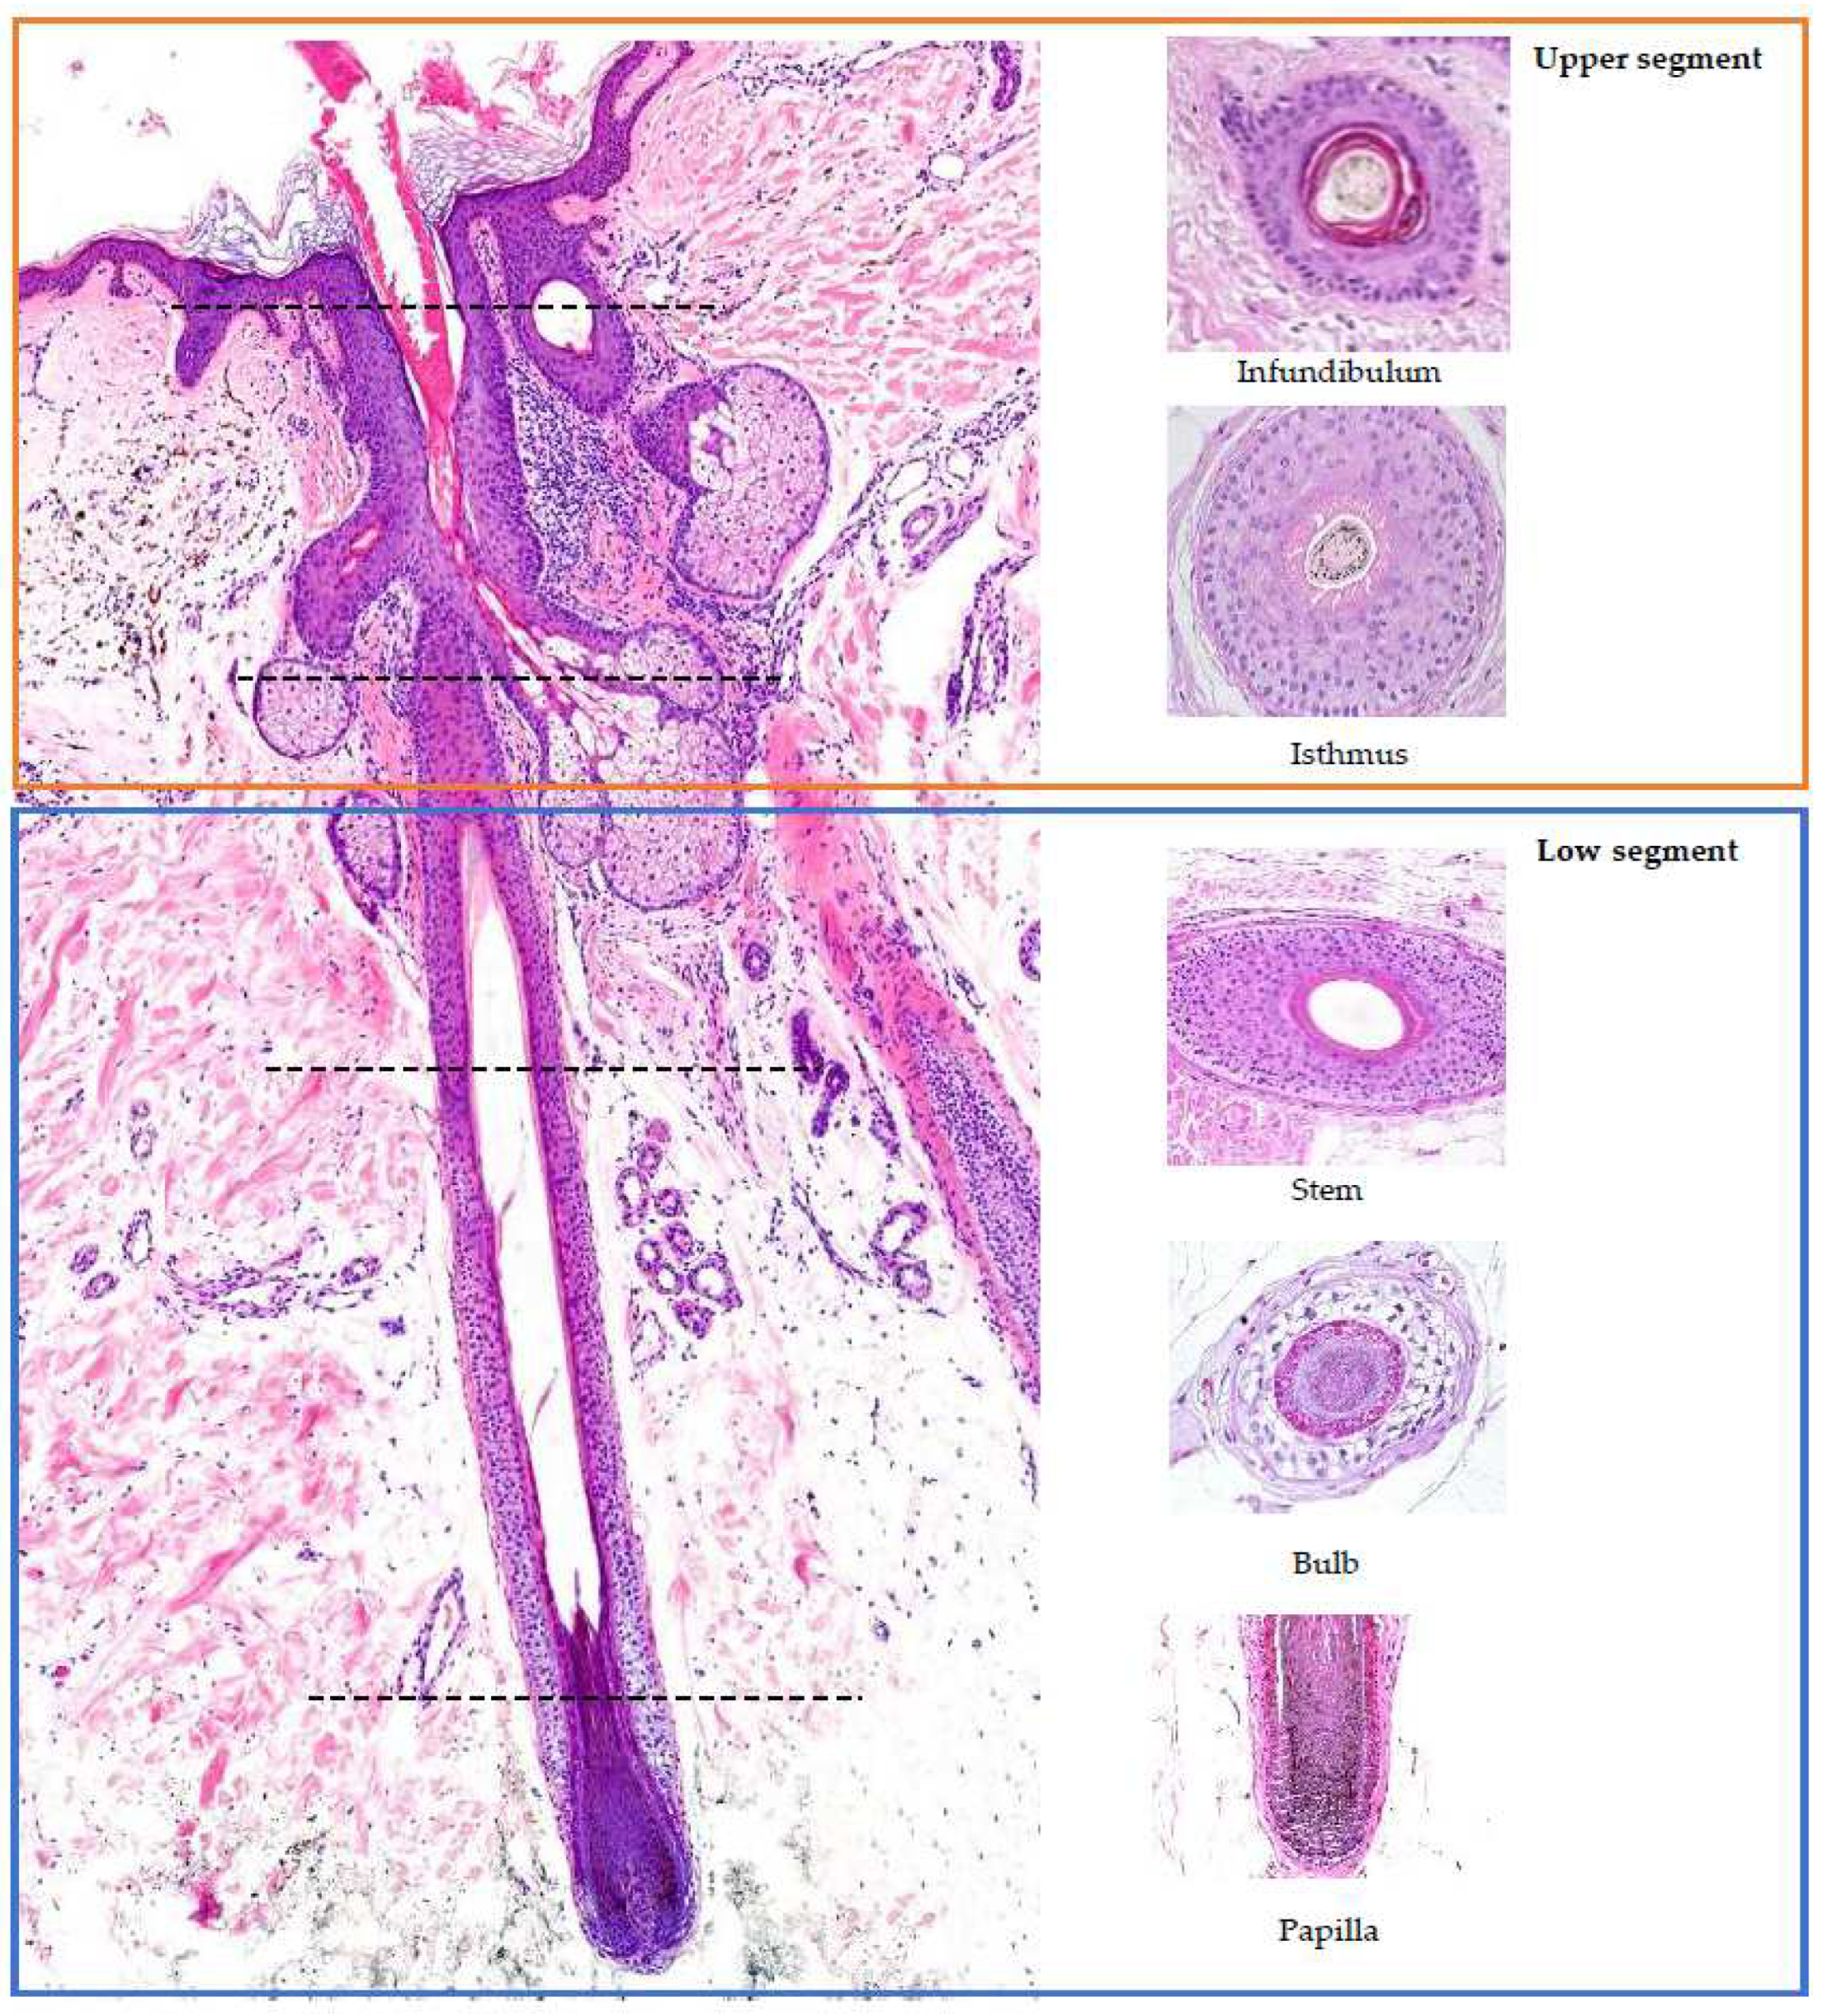

2. Hair Follicle Histology (Figure 1) [5,7,8,9,10]